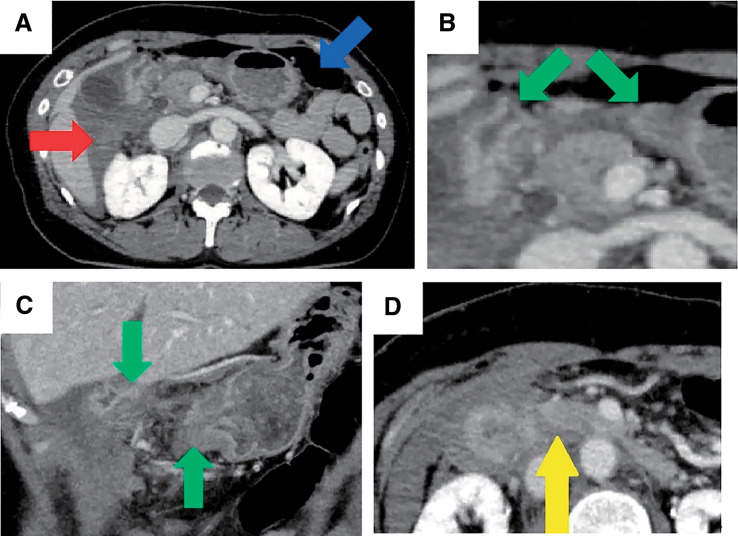

Case presentation: A woman in her 50s was kicked in the right upper quadrant of her abdomen by a horse and transported to a local hospital. Computed tomography revealed pneumoperitoneum and hematoma near the duodenum, discontinuity of the duodenal wall, and a poorly contrasted area in the pancreas head. The patient underwent emergent laparotomy 6h after the accident. The first portion of the duodenum was completely lacerated. No contamination around the pancreatic head or saponification of fat tissue was observed. Because the patient's vital signs were stable and the condition of the damaged tissue was favorable, the transection was repaired with trimming of the pyloric part of the stomach and end-to-end anastomosis between the gastric remnant and the duodenum. Decompression, feeding and biliary drainage tubes were placed. The patient's postoperative course was favorable and the patient was discharged on postoperative day 20 in a stable condition. At an outpatient visit 3 months postoperatively, the patient reported no abdominal pain or stenosis symptoms.